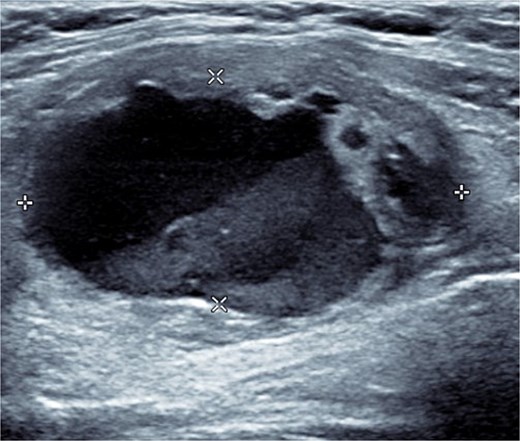

Bloods demonstrated elevated inflammatory markers with a neutrophil count of 7.53 and C-reactive protein of 137. Her biochemistry panel including thyroid function tests were within normal limits. An ultrasound (USS) was performed which showed a cystic/solid nodule in the left thyroid gland that measured 30 × 42 × 22 mm with an estimated volume of 14 ml (Fig. 1). A computed tomography (CT) scan was conducted to ensure no airway compression, it demonstrated the abscess to measure 32 × 26 × 32 mm (Figs 2 and 3). There was no tracheal compression but there was mild inflammatory stranding and hyperenhancement of the nodule consistent with infection.

USS of the thyroid demonstrating the cystic lesion in the left thyroid gland.